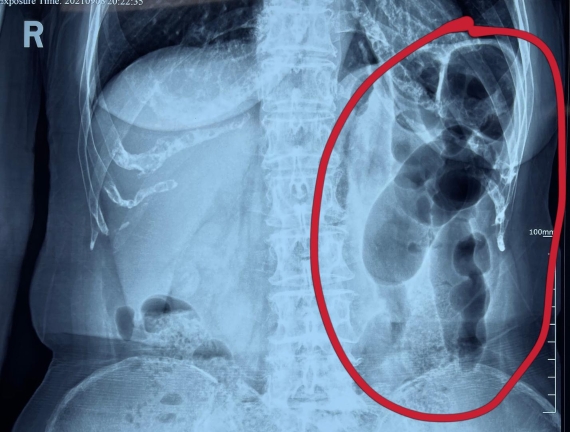

據省醫院消化病院消化二科姜子曄醫生介紹,韓大娘今年已經73歲,家住哈爾濱市,一周前開始腹脹腹痛,有較為明顯的左側腹部疼痛,疼痛劇烈時會出現左側腹部鼓包情況,排氣排便后有所好轉。韓大娘家人見狀將其送到了黑龍江省醫院,門診檢查腹部平片提示為左側腹部積氣,口服全消化動力藥及通便治療后腹痛腹脹有所緩解,入院前再次突發左側腹痛加重伴有明顯腹脹,急診隨后以“腹痛腹脹原因待查”將韓大娘收入到消化病院消化二科。

姜子曄醫生熱情接待了韓大娘,為其進行了仔細查體,除了左側腹部壓痛并未見明顯異常,對癥給予灌腸后,韓大娘的腹脹有所緩解,第二天姜子曄醫生為韓女士進行了胃腸鏡檢查,也未見明顯異常。但此時韓大娘腹部平片結腸腸管擴張仍然很嚴重,腹痛腹痛也沒緩解,到底什么原因呢?消化二科主任陸以霞在查房時建議繼續給予韓大娘口服全消化動力藥,必要時灌腸治療,同時陸以霞主任在追問病史查體時發現韓大娘左下腹紅色皮疹和小水泡,反復抓撓腹部皮膚部分已結痂,高度懷疑為帶狀皰疹。